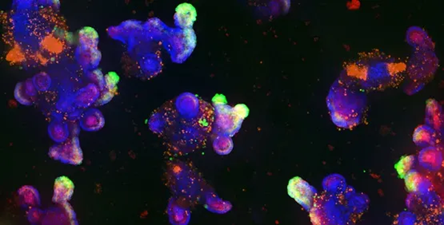

Patient-derived organoids (Tumoroids)

Image Credit: Molecular Devices UK Ltd

Patient-derived tumor organoids, also known as tumoroids, are tumor cell cultures obtained from individual patients. Patient-derived organoids (PDOs) are created from tumor biopsies or surgical procedures and can be used as models to study patient-specific medication responses and cancer cell proliferation.

Digested tumor fragments and cells taken from patient-derived tumors have cancer stem cell (CSC)-like properties and can be grown over numerous passages to produce huge numbers of organoids with the molecular characteristics of the original tumor.